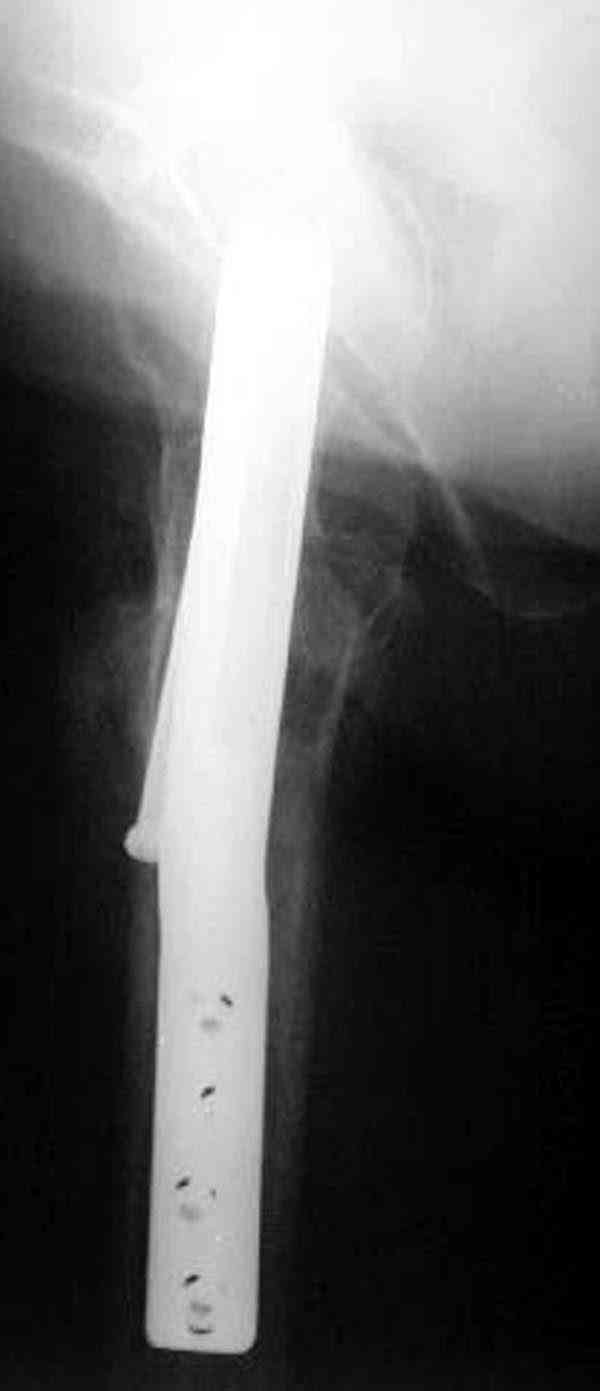

Здесь случай перелома из-за ослабления латерального кортекса через 3 недели после операции на шейке. Шурупы были установлены под большим углом, слабый латеральный кортекс не выдержал нагрузку.

Коллега Челноков прав, здесь еще имеется риск перелома за счет ослабления латерального кортекса. Во время установки канюлированных шурупов за редким исключением спица вводится с одного раза, множественные попытки ослабляют латеральный кортекс, что станет источником перелома в этом месте.

В идеале для профилактики рефрактуры шурупы надо вводить не больше, чем под 130 градусным углом и не ниже уровня малого вертела.